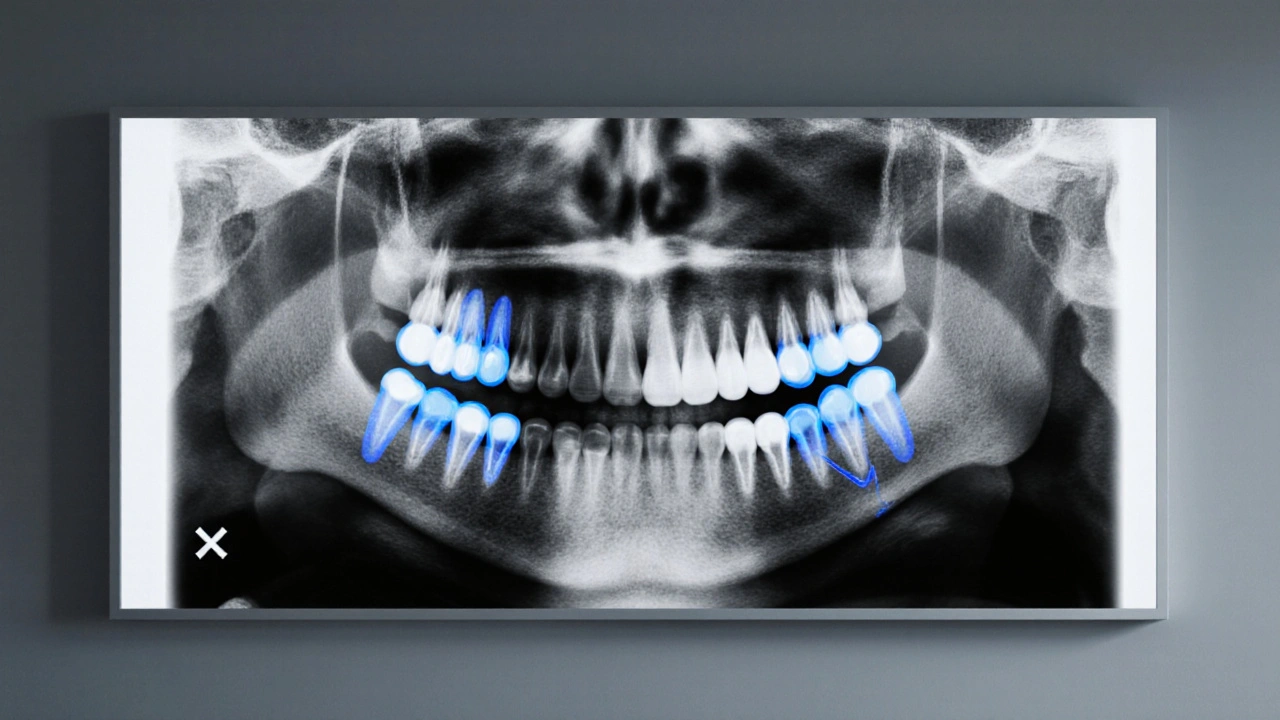

Druhou částí je radiologické vyšetření. rentgenové snímky (ortopantomogram) ukazují přesnou polohu a úhel růstu všech čtyř zubů moudrosti. V některých případech může být nutná 3D CT, aby se odhalily komplikace jako proximity k nervovým kanálům.